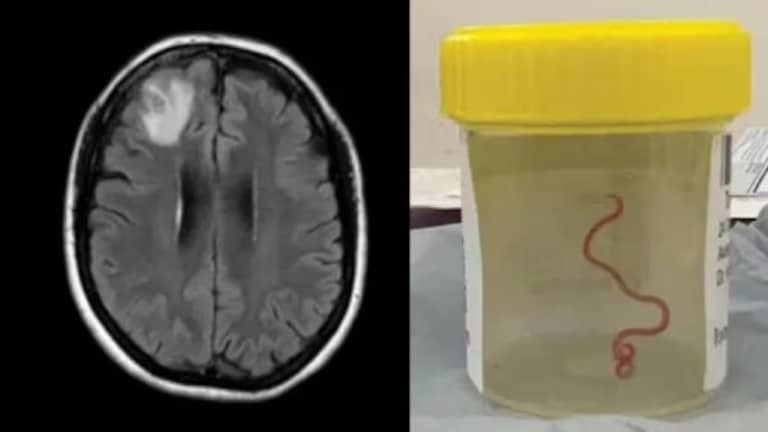

एका 64 वर्षीय महिलेच्या डोक्यात जिवंत किडा आढळून आल्याची धक्कादायक घटना समोर आली आहे. महिलेच्या मेंदूचा एमआरआयचा रिपोर्ट काढल्यानंतर ही बाब उघड झाली आहे. ही घटना कळताच डॉक्टरांना देखील आश्चर्याचा धक्का बसलाय

गेल्या 2021 पासून महिलेवर उपचार सुरु होते. महिलेला न्युमोनिआ, पोटदूखी, जुलाब, कोरडा खोकला, ताप आणि रात्री घाम येणे अशी सर्व लक्षणे दिसत होती. त्यानुसार डॉक्टरांनी तिला स्टेरॉईड आणि इतर औषधे देऊन तिचा उपचार सुरु केला होता. या उपचारा दरम्यान 2022 ला महिलेमध्ये डिप्रेशन आणि स्मृतिभ्रंशची लक्षणेही दिसू लागली. त्यामुळे डॉक्टरांनी तिला मेंदूचे एमआरआय स्कॅन करून सर्जरीचा सल्ला दिला होता. मात्र रिपोर्टमध्ये महिलेच्या मेंदूत किडा सापडल्याची धक्कादायक बाब समोर आली होती.

डोक्यात 3 इंच लांबीचा किडा

डॉक्टरांनी दिलेल्या माहितीनूसार, महिलेच्या डोक्यात आढळून आलेला किडा 3 इंच लांब, चमकदार लाल रंगाचा आहे. या किड्याला पॅरासाईट राउडवॉर्म म्हणतात. तर शास्त्रज्ञांमध्ये या किड्याला ओफिडास्कॅरिस रॉबर्टसी म्हणून ओळखले जाते. ही प्रजाती सापांमध्ये आढळते. राउंडवर्मचा हा विशिष्ट प्रकार कार्पेट पायथन्स (अजरग) मध्ये आढळतो,ही एक मोठी प्रजाती आहे. हे ऑस्ट्रेलिया, इंडोनेशिया आणि पापुआ न्यू गिनीमध्ये आढळतो.